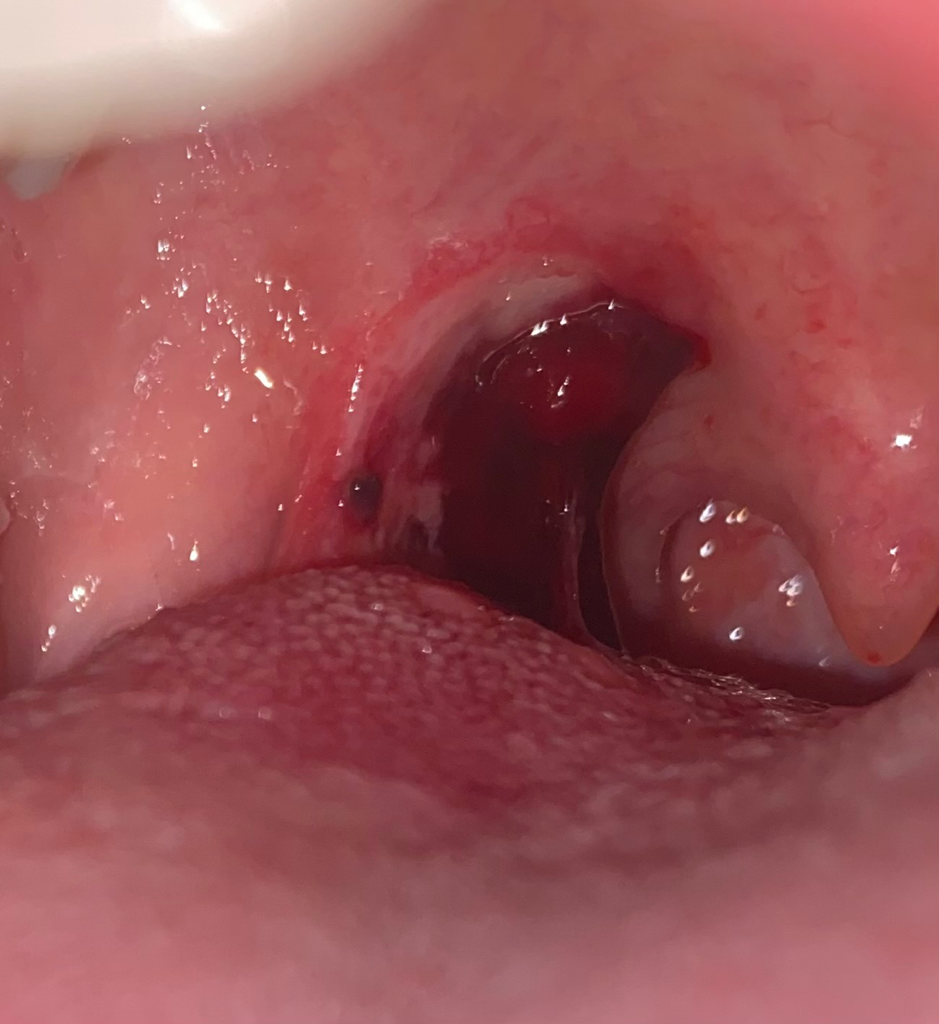

편도 제거 수술 5일차 출혈이 있는데 괜찮은 건가요?

편도 제거 수술 5일차인데 아침, 점심에 피가 약간씩 비치더니 2시간 전부터 피가 덩어리진 채로 수술 부위에 붙어있어요. 딱지가 떼어진 것 같기도 해요. 병원에서 피토할 때는 응급실에 가야 한다고 안내해주셨는데 이렇게 피가 덩어리졌을 땐 어떻게 해야 하는지 모르겠어요. 단순히 얼음 가글하면 되는 건지, 응급실에 가야 하는 건지 질문드려요. 그리고 저 피 덩어리는 그냥 냅두면 되나요?

• 1번 째 사진

출혈양이 적지는 않네요. 응급실에 가서 진료를 받으실 필요가 있을 것 같습니다

다른 조치를 취하실 경우 잘못하면 재출혈할 수도 있으니 그냥 응급실을 방문하세요

현재의 정도에서는 응급실을 가야할 정도는 아닌 것으로 보입니다. 출혈이 멈추지 않고 계속 소주잔 반잔 이상 뱉어 낼 때에는 응급실 진료가 필요할 것으로 보입니다

피 덩어리의 경우 출혈이 응고된 상태이기 때문에 무리하여 제거시 출혈이 다시 발생할 수 있습니다.

처방받으신 가글이 있으시다면 가글을 하여 자연스럽게 제거가 되도록 해주시고

출혈이 멈추지 않고 지속되는 경우는 수술병원에 내원하시어 내부상태 확인 및 지혈에 대해 진료를 받아보시는 것을 추천드립니다.